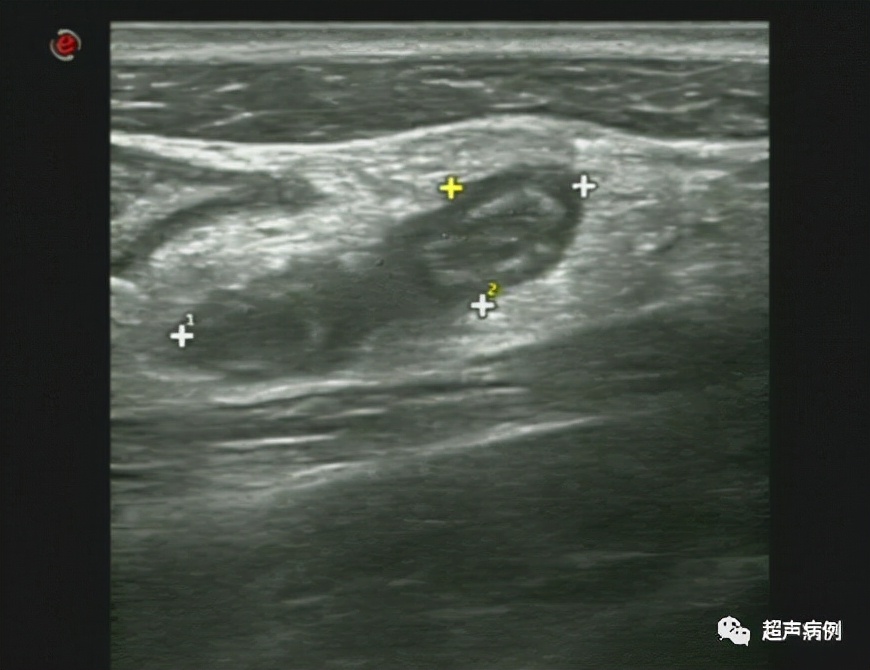

What Does Appendicitis Look Like On Ultrasound . — ultrasound is considered the imaging modality of choice for pediatric and pregnant patients where appendicitis is. Appendicitis is most commonly treated by. Acute appendicitis is the most common surgical emergency in children with higher incidence between. Ultrasound with its lack of ionising radiation should be the investigation of choice in young patients. — what does appendicitis look like on ultrasound? — acute appendicitis (aa) is a disease with a high prevalence, requiring rapid and accurate diagnosis to confirm or. ct is the most sensitive modality to detect appendicitis although its use should be limited because of the radiation dose. — an ultrasound or ct scan will usually show an enlarged appendix. — • ultrasound (us) should be the first imaging modality for diagnosing. — appendicitis is a frequent cause of abdominal pain. — the first steps are with the use of the appropriate imaging modality (us, ct and mri) to locate the appendix in abdominal cavity and to identify the features of appendicitis and its complications through specific imaging signs. by the end of this video, you'll be able to look at an ultrasound image and distinguish between a normal appendix and an inflamed one so that you can quickly identify and treat a case of appendicitis. — the most useful sign of acute appendicitis on ultrasonography is an outer appendiceal diameter of 6 mm or greater. While many cases of appendicitis are easy to diagnose clinically, a significant number need further workup. Symptoms may be atypical, and the appendix may not be.

— in a patient with undifferentiated right lower quadrant pain, appendicitis is often at the top of the. — • ultrasound (us) should be the first imaging modality for diagnosing. by the end of this video, you'll be able to look at an ultrasound image and distinguish between a normal appendix and an inflamed one so that you can quickly identify and treat a case of appendicitis. The appendix will be greater than 6 mm in outer diameter. Acute appendicitis is the most common surgical emergency in children with higher incidence between. Ultrasound with its lack of ionising radiation should be the investigation of choice in young patients. — an ultrasound or ct scan will usually show an enlarged appendix. Appendicitis is most commonly treated by. — acute appendicitis (aa) is a disease with a high prevalence, requiring rapid and accurate diagnosis to confirm or. — ultrasound is considered the imaging modality of choice for pediatric and pregnant patients where appendicitis is.

Appendicitis Critical Care Sonography What Does Appendicitis Look Like On Ultrasound — the most useful sign of acute appendicitis on ultrasonography is an outer appendiceal diameter of 6 mm or greater. Ultrasound with its lack of ionising radiation should be the investigation of choice in young patients. While many cases of appendicitis are easy to diagnose clinically, a significant number need further workup. Appendicitis is most commonly treated by. . What Does Appendicitis Look Like On Ultrasound.